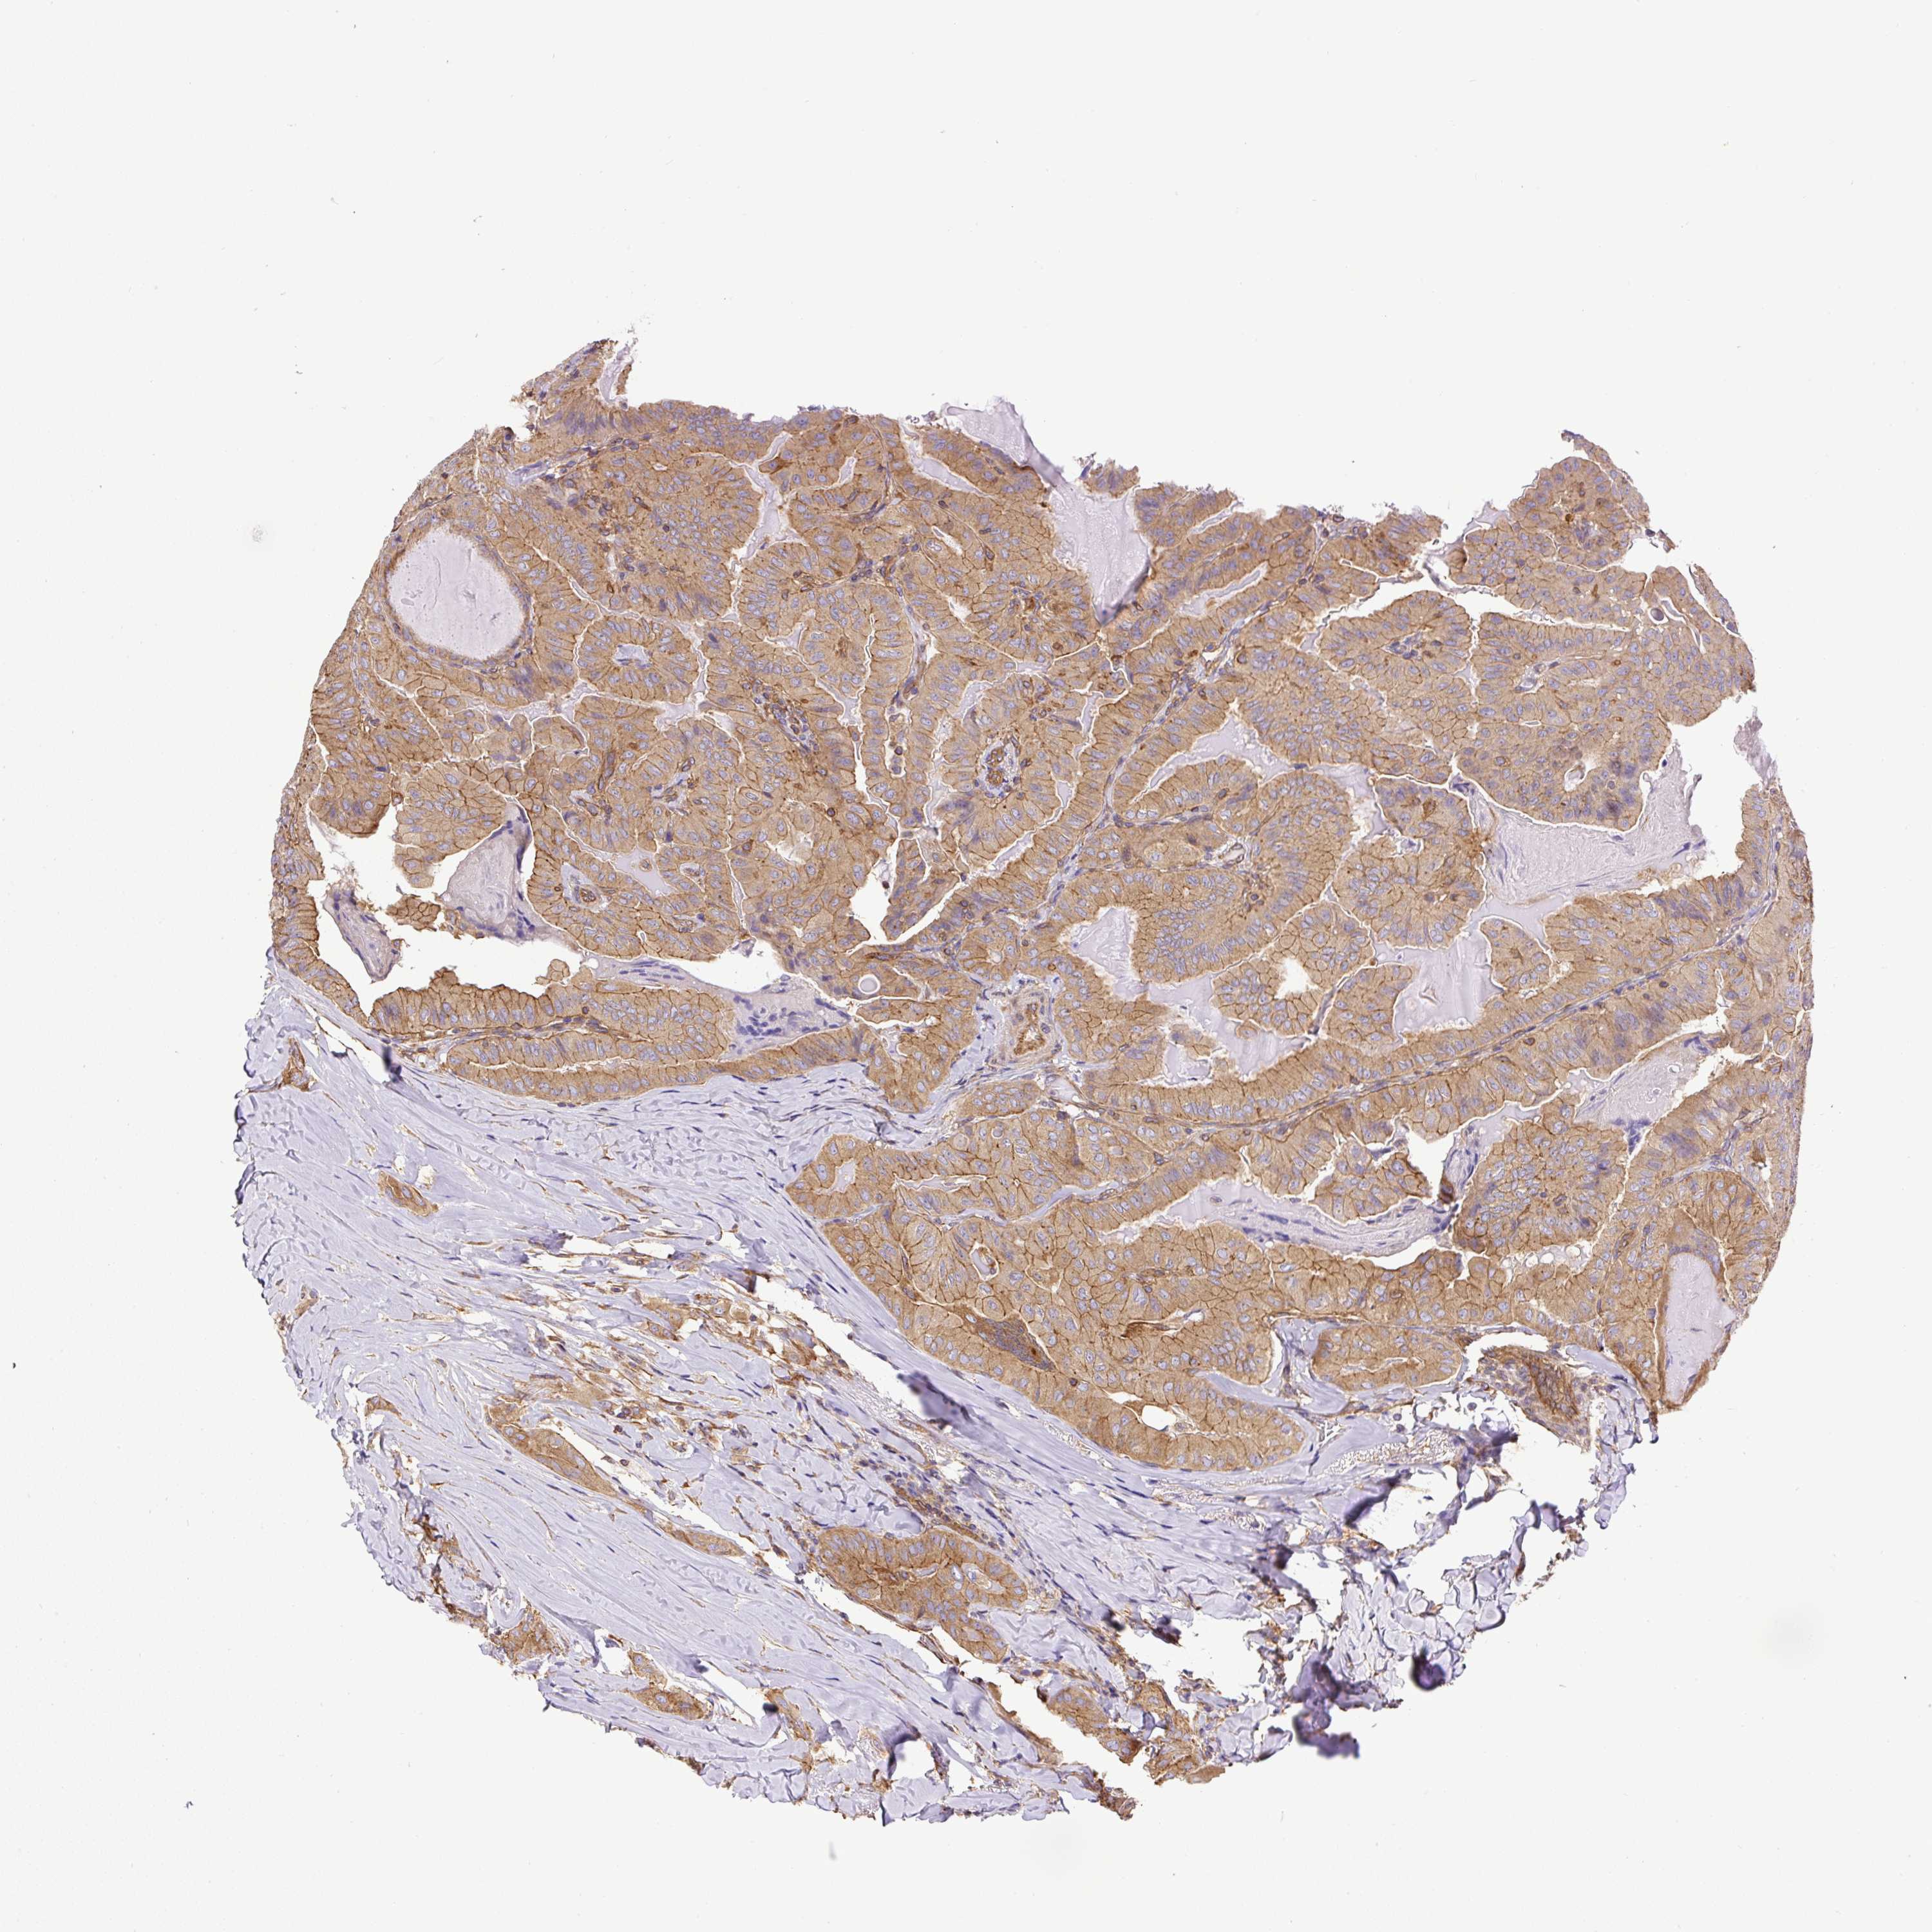

THYROID CANCER - Protein expressioni

A mouse-over function shows sample information and annotation data. Click on an image to view it in a full screen mode. Samples can be filtered based on level of antibody staining by selecting one or several of the following categories: high, medium, low and not detected. The assay and annotation is described here.

Note that samples used for immunohistochemistry by the Human Protein Atlas do not correspond to samples in the TCGA dataset.

Antibody stainingi

Antibody staining in the annotated cell types in the current human tissue is reported as not detected, low, medium, or high, based on conventional immunohistochemistry profiling in selected tissues. This score is based on the combination of the staining intensity and fraction of stained cells.

Each image is clickable and will lead to virtual microscopy that enables deeper exploration of all samples and also displays staining intensity scores, fraction scores and subcellular localization as well as patient and tissue information for each sample.

Antibody HPA034635

Antibody HPA069977

Antibody HPA071875

Antibody CAB009108

Staining

High

Medium

Low

Not detected

Intensity

Strong

Moderate

Weak

Negative

Quantity

>75%

75%-25%

<25%

None

Location

Nuclear

Cytoplasmic/membranous

Cytoplasmic/membranous,nuclear

Papillary adenocarcinoma, NOS

Follicular adenoma carcinoma, NOS